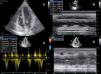

She had gone to the emergency department (ED) 48 hours before due to syncope with spontaneous recovery and flu-like symptoms for seven days. There were no alterations on initial physical examination, electrocardiogram (ECG) or brain computed tomography (CT). Laboratory tests showed increased inflammatory parameters (white cell count 23900/m3 with 85% neutrophils and C-reactive protein 2.83 mg/dl) and elevated troponin I (2 μg/l). During observation in the ED the patient developed shock and was transferred to the general intensive care unit, where transthoracic echocardiography (TTE) revealed non-dilated cardiac chambers, mild hypertrophy of the left ventricular (LV) walls, biventricular dysfunction and mild circumferential pericardial effusion (Figure 1).

Transthoracic echocardiography after onset of shock, showing biventricular dysfunction and mild circumferential pericardial effusion. (A) Apical 4-chamber view showing mild hypertrophy of the left ventricular walls (probably edema); (B) M-mode assessing ventricular dimensions and left ventricular function; (C) left ventricular outflow tract velocity-time integral, an indirect measure of left ventricular function; (D) right ventricular function assessed by tricuspid annular plane systolic excursion. LVOT: left ventricular outflow tract; TAPSE: tricuspid annular plane systolic excursion; VTI: velocity-time integral.

A diagnosis of CS was made, confirmed by Swan-Ganz catheter, which showed cardiac output of 2 l/min, cardiac index of 1.2 l/min/m2, and systemic vascular resistance of 1438 dyn s/cm5. A provisional diagnosis of fulminant myocarditis was made; the pericardial effusion raised the suspicion that the pericardium was involved, but there was no ECG evidence or history of pain that would suggest pericarditis. The chest X-ray at admission showed no abnormalities (Figure 2A).

In the present case, the diagnosis was based on clinical criteria. TTE was important to identify the type of shock, exclude other causes of CS (tamponade, valvular disease, tumor, Takotsubo or restrictive cardiomyopathy, endocarditis or LV outflow tract obstruction), and to monitor the response to therapy.

The echocardiographic findings were in line with those reported in other cases. In a study by Pinamonti et al.6 in patients with fulminant myocarditis, LV dysfunction was seen in 69% of cases and right ventricular dysfunction in 23%; LV dilatation was rare. LV hypertrophy was seen in four of these patients, also observed by Felker et al.,7 associated with the marked inflammatory response seen on EMB, the resolution of which was associated with reduced edema (and thus hypertrophy) and improvement in LV function.